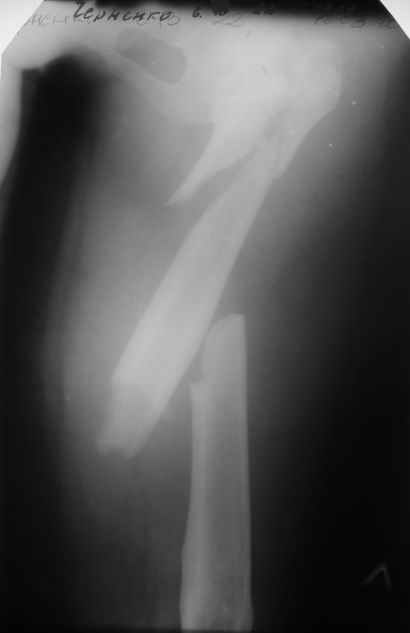

Пациентка 23 лет, доставлена в клинику с Диагнозом: Закрытый сегментарный оскольчатый перелом левой бедренной кости в верхней и средней трети. Травма в результате ДТП 10.03.2006г. Из анамнеза у пациентки диспластический левосторонний коксартроз, S-образный сколиоз 2ст. В 1999г в Кургане выполнялась остеотомия бедра в нижней трети и коррекция укорочения конечности на 3 см (рентгенограммы бедра и таза до травмы в приложении). До получения травмы пациентка ходила без боли с полной нагрузкой на левую ногу. Учитывая дисплазию левого ТБС, пациентке, вероятно, предстоит операция тотального эндопротезирования лев ТБС, что требует анатомичного восстановления проксимальногоотдела бедра. Рассматриваются следующие вариант остеосинтеза:1) Экстракортикальный остеосинтез проксимального и дистального перелома пластиной с угловой стабильностью типа LISS( г Рыбинск); 2) Ретроградный интрамедуллярный блокированный остеосинтез дистального перелома и накостный синтез проксимального пластиной с угловойстабильностью; 3) Остеосинтез бедра в аппарате внешней фиксации с фиксацией таза и возможной открытой адаптацией фрагментов. Хотелось бы узнать Ваше мнение. С уважением Украинский Евгений, г.Краснодар, ККБ N1, ТОО N3.

Уважаемые коллеги, приношу извенения за молчание. Готовили материал и боялись писать раньше времени. Все хотели убедиться в том, что после операции все будет спокойно. Спасибо за отклики и советы. К сожалению, гамма-гвоздя, штифтов с возможностью установки более 2-х блокирующих винтов у нас нет. Зато нашли достаточно длинную пластину с угловой стабильностью. После проведения предоперационной подготовки и планирования выполнили остеосинтез. В условиях рентгеноперационной, после репозиции дистрактором из одного разреза 5см в проксимальном отделе подкожно установили пластину. Пришлось выполнить дополнительный разрез до5см в проекции перелома диафиза в средней трети, из которого удалось репонировать перелом и выполнить фиксацию стягивающим винтом. Затем все завершилось наложением пластины с угловой стабильностью. Пластина оказалась достаточно длинной, что позволило перекрыть все переломы с фиксацией каждого отломка минимум 5-ю винтами. Синтез достаточно стабилен. Пациентка активизирована на 3-и сутки(снимки прилагаются). В настоящий момент пациентка выписана на амбулаторное лечение. Еще раз, огромное спасибо всем за помощь в выборе тактики и просто совете. С уважением Украинский Е.